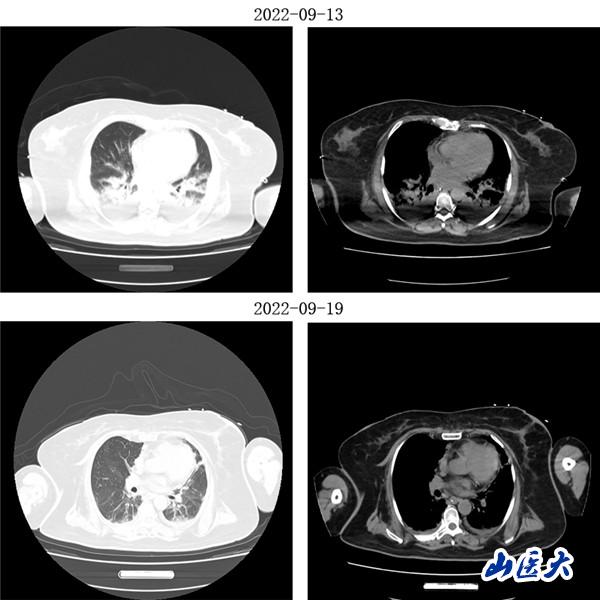

重症医学科三病区张文凯主任团队深入分析了两位患者的病情。考虑到两名老年患者均已出现急性呼吸窘迫综合征,决定采用俯卧位通气技术为他们治疗。在张文凯主任的指导下,侯林义主治医师带领张承、孙洁住院医师对女性患者经俯卧位通气治疗,92小时后复查胸部CT,双肺明显好转,氧合指数由90上升至300mmHg以上,吸氧浓度由100%降至35%,ARDS明显改善;对男性患者,采用联合持续性血液滤过(CRRT)治疗方案,经俯卧位通气治疗66小时后复查胸部CT,显示明显改善,同时氧合指数由102上升至360mmHg左右,吸氧浓度需求下降至40%,全身水肿情况也明显减退。

(女性患者治疗前后胸部CT对比)